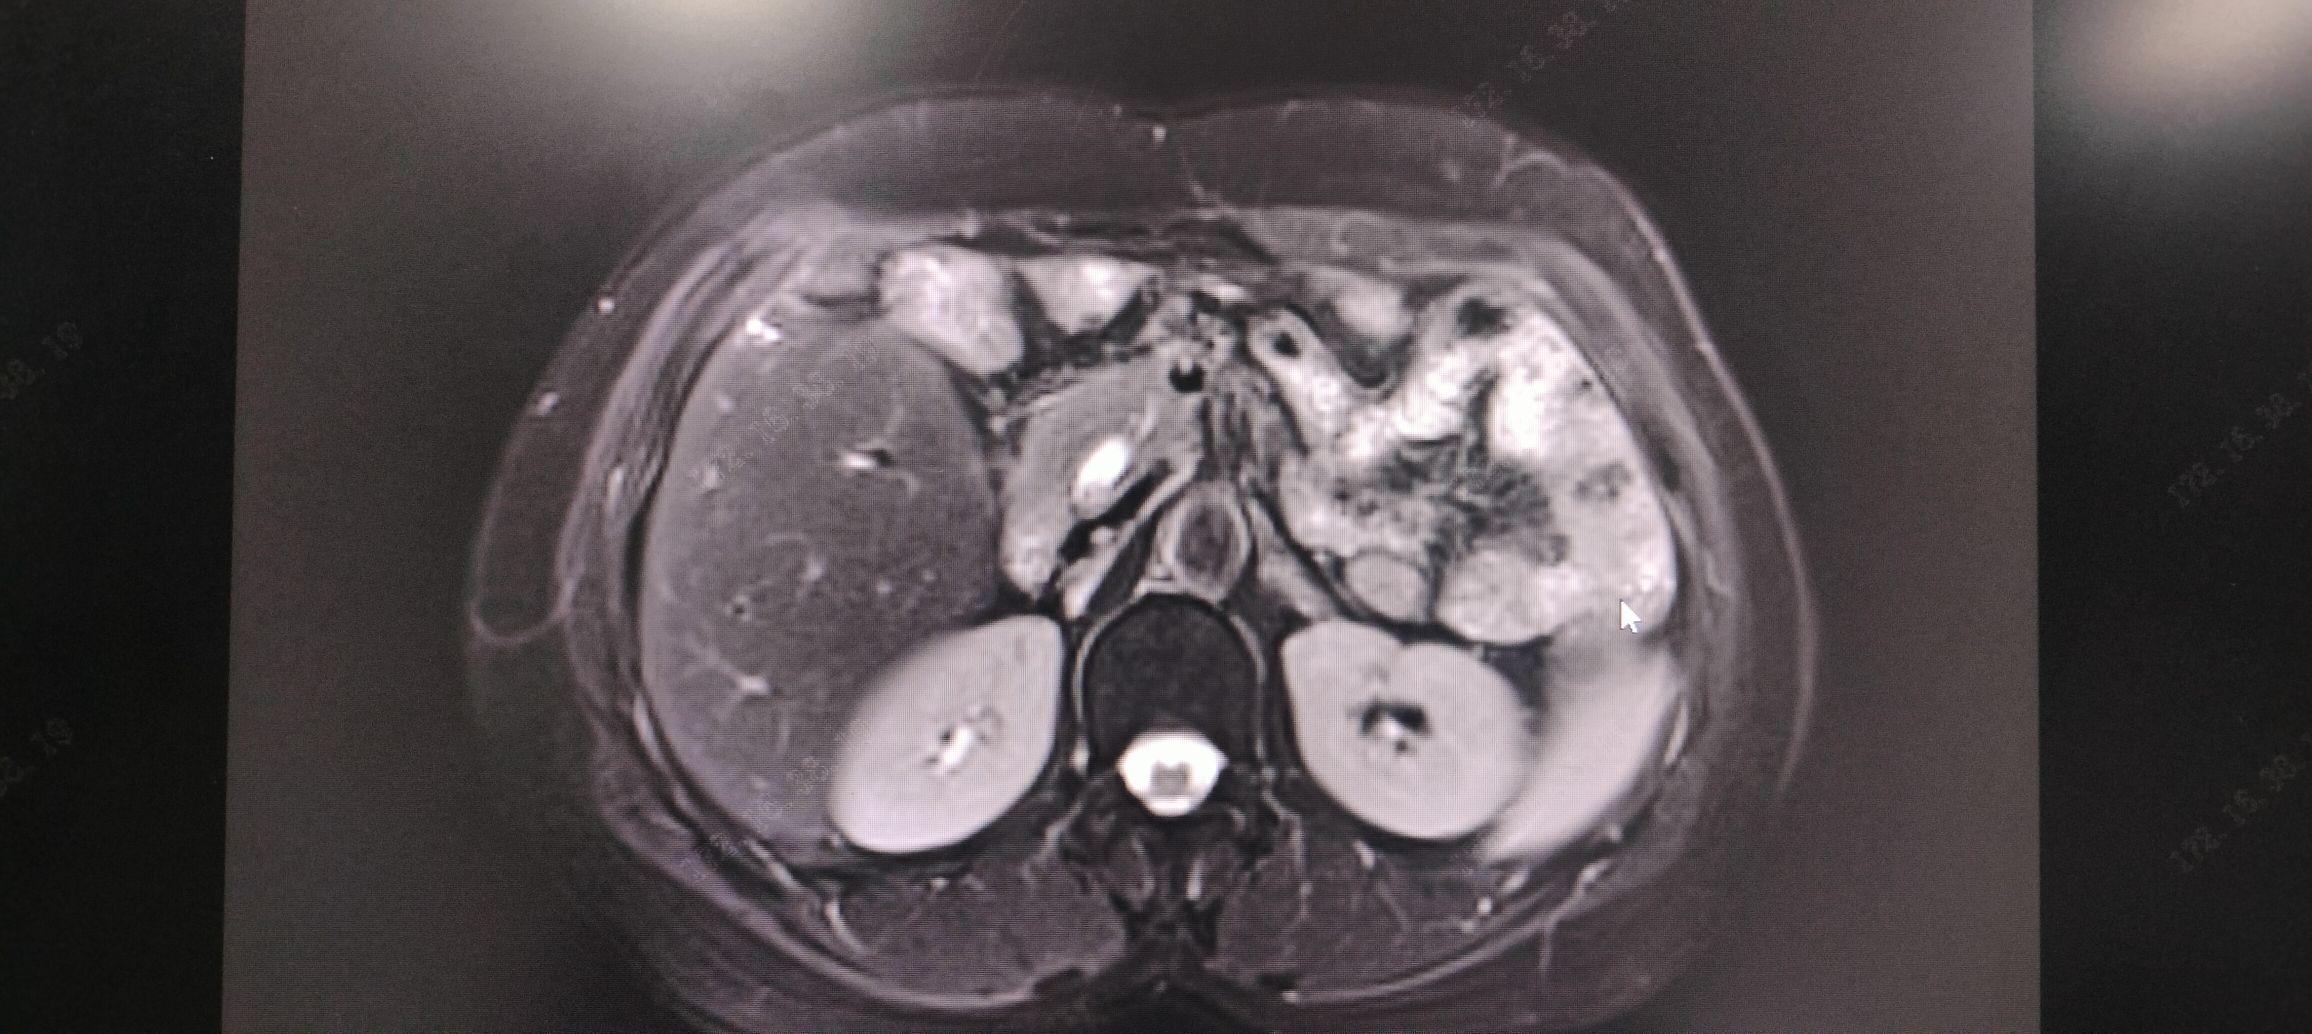

2025-09-17 CT检查报告:检查结果胆道结石并梗阻扩张。2025-09-17 DR检查报告:心肺膈肌未见明显异常。2025-09-18 MR检查报告:1.胆总管下段、肝左叶胆管多发结石伴梗阻。2.肝左叶异常信号影,考虑炎性改变、萎缩,请结合临床,必要时建议增强。3.肝门区肿大淋巴结。请结合临床、随诊。2025-09-18 超声检查报告:1.肝内胆管结石并肝内胆管扩张;2.胆总管扩张;3.胰、脾未见明显异常。2025-09-17 生免检验报告:丙氨酸氨基转移酶 66.1U/L,天门冬氨酸氨基转移酶 63.2U/L,碱性磷酸酶 208U/L ,-谷氨酰基转移酶 131U/L 总胆红素 11.6umol/L, 直接胆红素 4.4umol/L, C反应蛋白 56.5mg/L。2025-09-17 血常规:白细胞 3.43*10^9/L , 红细胞3.7*10^12/L, 血红蛋白 112g/L , 红细胞压积 33.5% , 血小板 185*10^9/L, 中性粒细胞比率 66.5%。凝血功能大致正常。肾功能、心肌酶谱、电解质、血糖未见异常。

【临床诊断】1.胆总管结石伴胆管炎 2.肝内胆管结石伴胆管炎

1.胆总管结石伴胆管炎

2.肝内胆管结石伴胆管炎